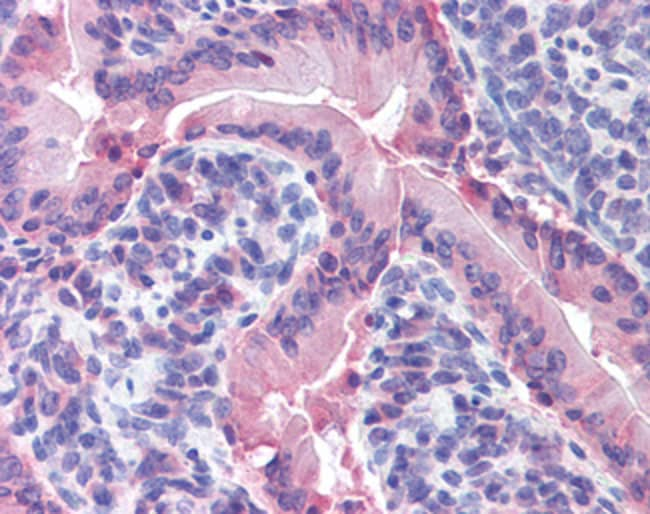

Aplicaciones Immunohistochemistry (Paraffin), Western Blot

IDO1 is an intracellular heme-containing enzyme that catalyzes the oxidative cleavage of the indole ring of several important regulatory molecules like tryptophan, serotonin, and melatonin. By doing this, IDO1 initiates the production of biologically active metabolites, commonly referred to as kynurenines. IDO1 is widely expressed in a variety of human tissues as well as in macrophages and dendritic cells (DCs). In inflammation, interferons (IFNs) act on specific receptors to trigger IDO1 induction. The production of IFN-gamma and induction of IDO1 represent important antimicrobial mechanisms. Degradation and depletion of tryptophan by IDO1 inhibits the growth of viruses, bacteria and parasites. Furthermore, IDO1 plays a complex and crucial role in immunoregulation during infection, pregnancy, autoimmunity, transplantation, and neoplasia.